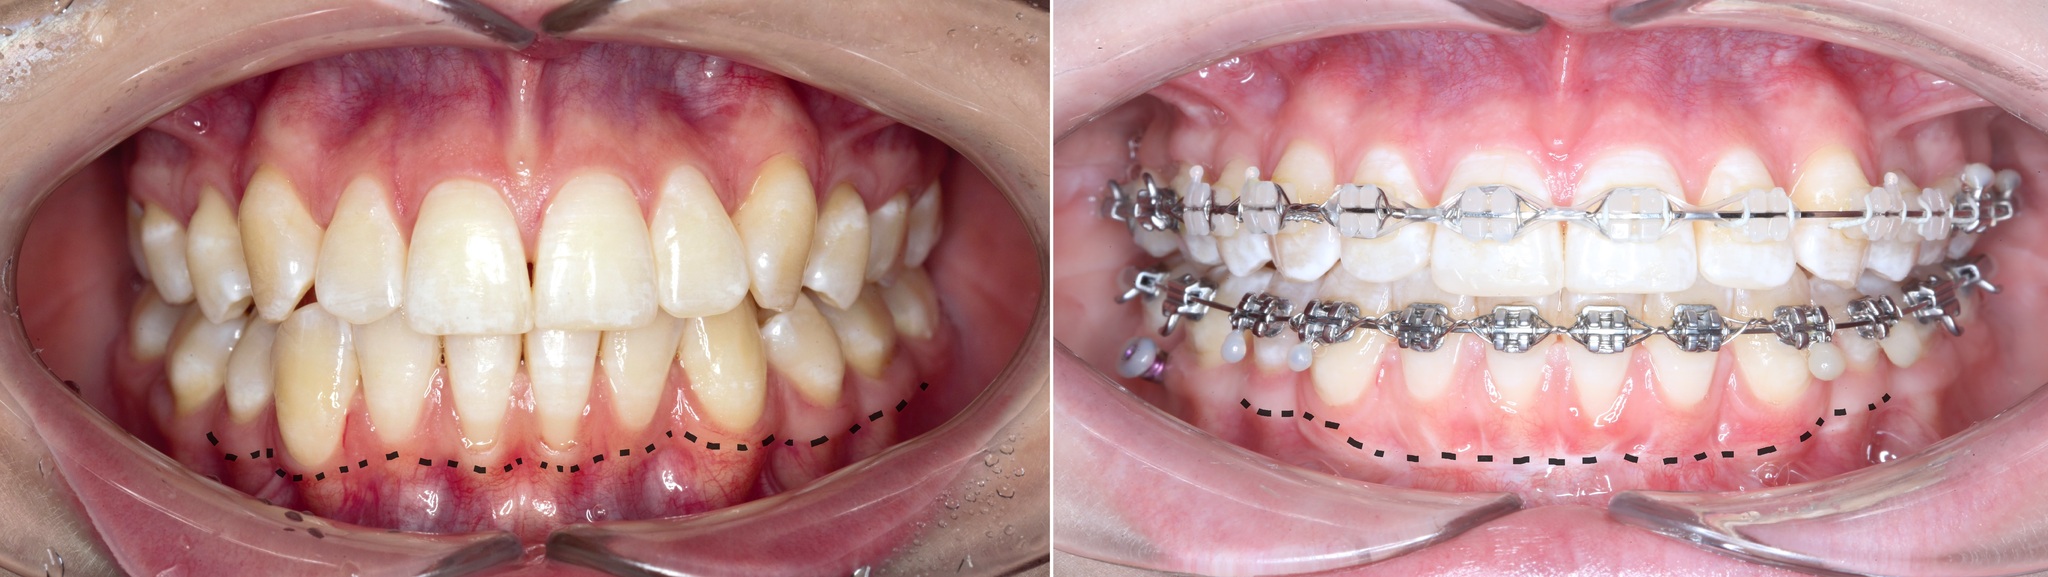

Чуть больше года назад в нашу (не побоюсь этого слова) уютную клинику на консультацию к ортодонту пришла девушка, возжелавшая исправить прикус и решить проблему рецессий десны в области нижних центральных зубов. Причина рецессий нумеро уно – это перегрузка зубов из-за неправильного их смыкания. Проще говоря, патологического прикуса. Поэтому нет вообще никакого смысла проводить закрытие рецессий без исправления прикуса. Деньги отдали, «эмоции» получили, а через какое-то время все снова стало так, как было (и это в лучшем случае).

Фотографии, сделанные на первичной консультации:

Ниже пунктиром отмечен переход подвижной слизистой в неподвижную. В некоторых местах, особенно в области центральных резцов прикрепленной десны, практически нет. В связи с чем образовались такие явные рецессии. Видно?